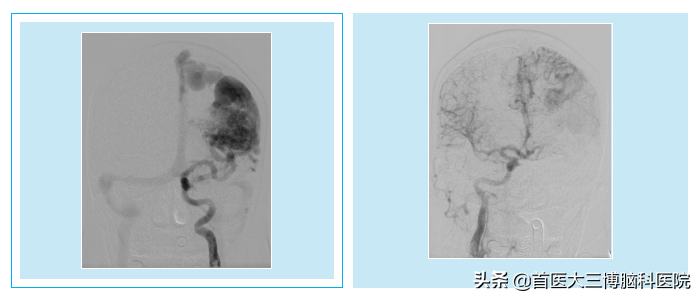

妊娠27周孕妇突发脑出血多学科协作紧急救治 首医大三博脑科医院 Mdeditor